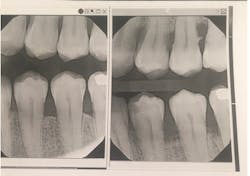

In the second, you can see the difference in bleeding after the patient used the interdental cleaners for just one week.